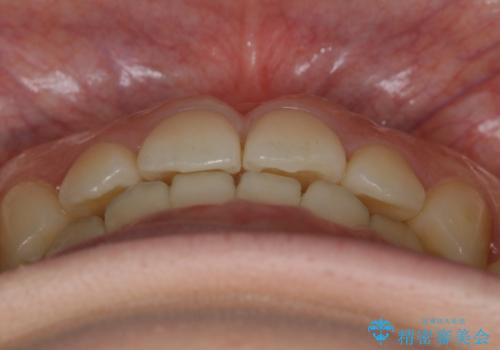

- 上の前歯のすきっ歯と下の前歯のガタつきを主訴にご来院されました。

噛み合わせの改善も同時に進めつつ、主訴の部分も効率的に治していくためマウスピース装置でゴムかけを行いながら治療を進めていきました。

正中離開(すきっ歯)

真ん中の歯が左右に開いてしまい隙間ができてしまう状態を「正中離開」といい、俗にすきっ歯と呼ばれています。

隙間を埋めていく方向に歯を移動させることで改善していくケースが多く、比較的治りやすい不正咬合のひとつとされています。

しかしながら、歯が捻じれていたり、噛み合う歯との位置関係によっては治療が難しくなる場合があります。